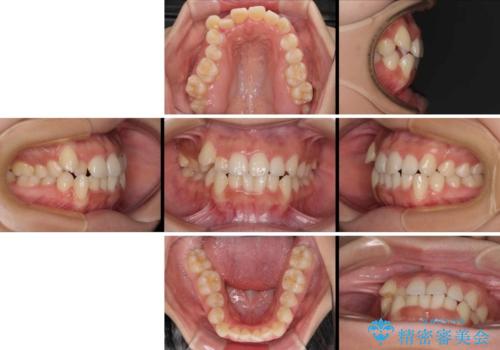

- 上下前歯のデコボコを気にして来院された患者様です。

上顎歯列が下顎の歯列に対して狭小であり、一部下顎の奥歯が上顎よりも外側に位置している状態でした。

上顎の急速拡大装置を使用して上顎骨を側方に拡大することで上顎歯列を拡大し、下顎歯列も拡大できるようにすることで、歯列を整えることとしました。